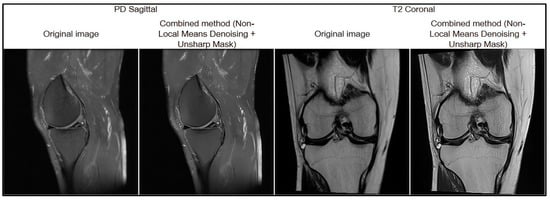

For a visual assessment of the effectiveness of each filter, Figure 4 presents the image preprocessing results obtained using the tested algorithms. The displayed MRI image fragments allow a visual comparison of the degree of noise suppression and the preservation of anatomical details for each method.

Figure 4.

Results of image processing using various methods.

Based on the results of the comparative analysis, the combined approach of Non-Local Means Denoising and Unsharp Mask was selected, as it demonstrated the best quantitative performance (MSE = 32.55; PSNR = 41.37; SSIM = 0.92), indicating its high effectiveness in MRI image preprocessing. In addition, this method produced the most visually satisfactory results, achieving optimal noise suppression while preserving anatomical boundaries (Figure 5).

Figure 5.

Result of filtration preprocessing.